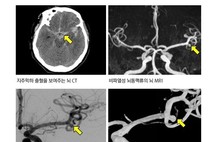

한국헬스경제신문 박건 기자 | 2022년 5월 배우 강수연씨가 잠을 자던 중 사망했다. 사인은 뇌동맥류 파열로 인한 뇌출혈이었다. 뇌동맥류(腦動脈瘤, cerebral aneurysm)는 뇌혈관(동맥)의 벽이 약해져 풍선이나 꽈리처럼 부풀어 오른 상태를 말한다. 한자 ‘瘤’는 ‘혹’이라는 뜻이다. 동맥의 벽은 여러 겹으로 이루어져 있는데, 일부 부위가 선천적·후천적으로 약해지면 혈압에 의해 그 부분이 점점 늘어나 주머니(혹)처럼 된다. 주로 뇌혈관이 갈라지는 분지점에서 잘 생긴다. 작은 뇌동맥류는 증상이 없지만, 무증상으로 지내다가 파열되면 ‘머릿속 시한폭탄’이라 불릴 정도로 심각한 뇌출혈을 유발한다. 한 번 터지면 사망률이 50~60%에 이른다. 살아남더라도 3명 중 1명에겐 중증장애가 남는다. 건강검진에서 발견되는 사례가 늘지만, 여전히 파열 후 응급실로 실려 오는 환자가 많다. 뇌동맥류는 대부분 뚜렷한 증상 없이 진행되지만, 동맥류가 급격히 자라면서 주변 뇌신경을 압박하면 ‘두통’, ‘복시(사물이 겹쳐 보임)’, 요통, 의식 저하 등 증상이 나타날 수 있다. 안검하수가 나타나기도 한다. 뇌동맥류가 눈꺼풀을 움직이는 신경이 마비시킬 수 있어서다. 뇌동맥류